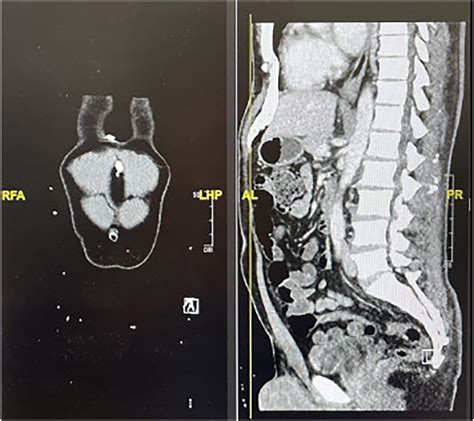

Candidates for this procedure often present with symptoms that include shortness of breath, chest pain, dizziness, and swelling in the legs or abdomen. When diagnostic imaging, such as an echocardiogram, confirms that the fluid is compromising cardiac output, the medical team will prioritize the surgical opening to stabilize the patient's hemodynamics.

Before undergoing the Pericardial Window Procedure, patients must undergo thorough preoperative evaluations. This includes blood tests, electrocardiograms (ECG), and chest X-rays to assess the severity of the effusion. Because the heart is directly involved, patients are typically placed under general anesthesia to ensure they are comfortable and still throughout the surgery.